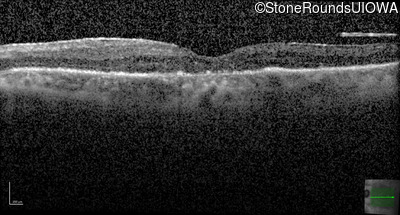

Optical Coherence Tomography - Right - 20/32

Exemplar / OCT Stack

OCT Stack